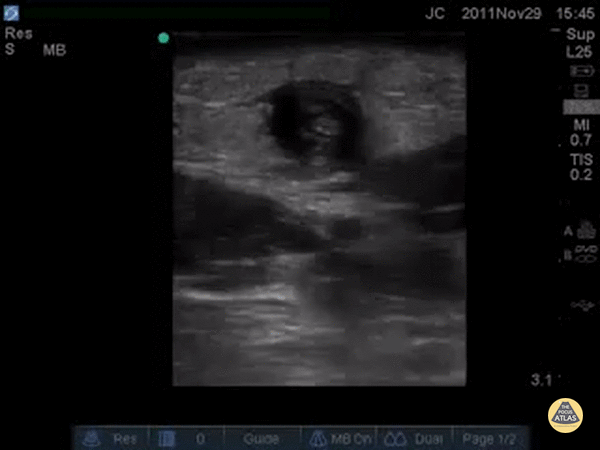

Vascular - Cephalic Vein Thrombophlebitis

Patient with pain and swelling to area above the antecubital fossa where an IV had been the week before, a palpable cord was appreciated proximal to the former IV site. POCUS demonstrated a clot, likely septic thrombophlebitis secondary to IV site infection. This is a similar techinque as what is done for DVT by finding the vessel, looking for a clot, and seeing if the vessel can be compressed. Dr. Bowra et al. (Dr. Chiang)